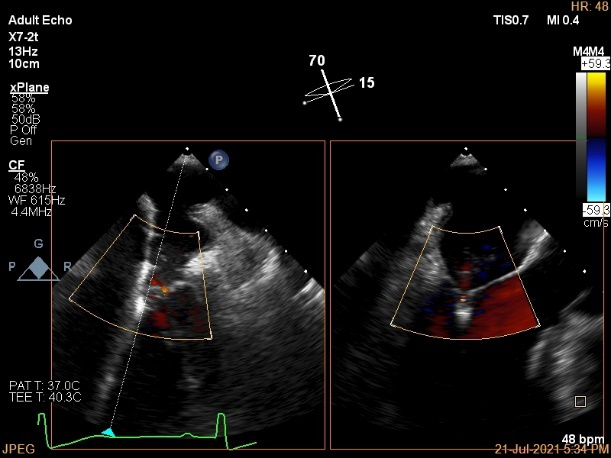

术中超声引导:

确定房间隔穿刺点:靠后

穿刺点高度测量:4.14cm

2D视图下测量大鞘长度2.2cm

2D视图下建立trajectory

3D视图打开夹子

3D视图下调Rotate,定位2区

X-plane:下夹子尝试捕获2区

夹子逐渐夹闭后,2区返流逐渐减少

3D:测量前叶长21.2mm,后叶长10.2mm

X-plane:计算前叶捕获长度6.8mm,后叶捕获长度6.5mm

夹子放置后二尖瓣口平均跨瓣压差:3mmHg

肺静脉血流频谱恢复正常

3D视图下观察二尖瓣双孔形态

3D-color:残余少量返流